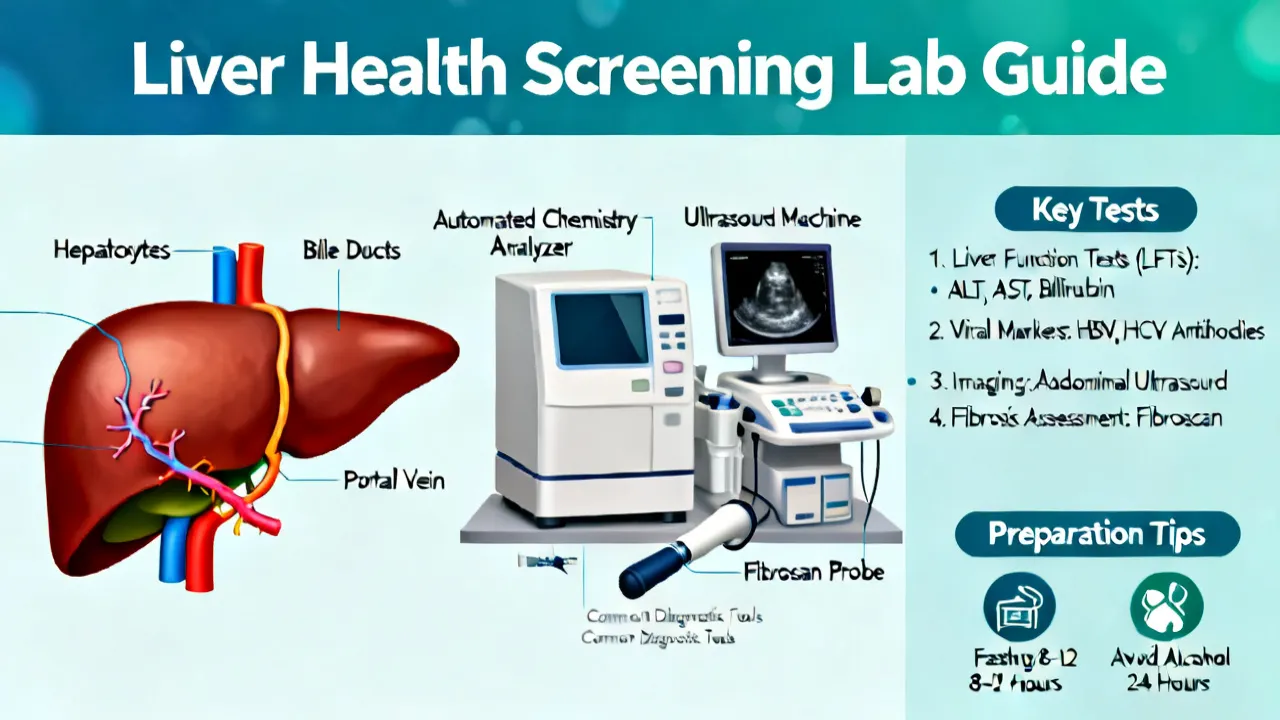

NASH HCC Screening is crucial for early detection and management of liver complications such as non-alcoholic steatohepatitis and hepatocellular carcinoma. Screening helps in identifying individuals at risk before symptoms develop. With advancements in medical technology, screening has become more precise, providing hope for better therapeutic outcomes and patient care in the ongoing battle against liver diseases.

NASH HCC screening plays a crucial role in the early detection of liver cancer associated with Non-Alcoholic Steatohepatitis (NASH). NASH is a severe form of non-alcoholic fatty liver disease that can progress to hepatocellular carcinoma (HCC), a common type of liver cancer. This article provides insights into the importance of screening, methods, and current practices in managing and identifying at-risk individuals for timely intervention.

NASH HCC Screening is a crucial process in the early detection of liver cancer associated with Nonalcoholic Steatohepatitis (NASH). As liver disease has become a growing concern, screening provides valuable insights into patient liver health, aiding in timely treatment strategies. This article delves into the significance, procedures, and advancements in NASH HCC Screening, providing a comprehensive guide from an expert's perspective.

Understanding the implications of Nash Hcc Screening is crucial in medical diagnostics, particularly for liver-related health issues. With advancements in medical technology, Nash Hcc Screening has emerged as a pivotal procedure in identifying and managing conditions affecting liver health, notably Nonalcoholic Steatohepatitis (NASH) and Hepatocellular Carcinoma (HCC). This comprehensive article delves into the significance, process, and advancements in Nash Hcc Screening, offering insights from medical experts on its role in predictive diagnostics and patient management.

Analyzing the significance of Nash Hcc Screening, this article explores its role in early detection of liver complications. "Nash", or Nonalcoholic Steatohepatitis, leads to cancer if unchecked. Early screening is key for prevention. The article offers expert insights on screening processes, benefits, challenges, and potential technological advancements in the field.